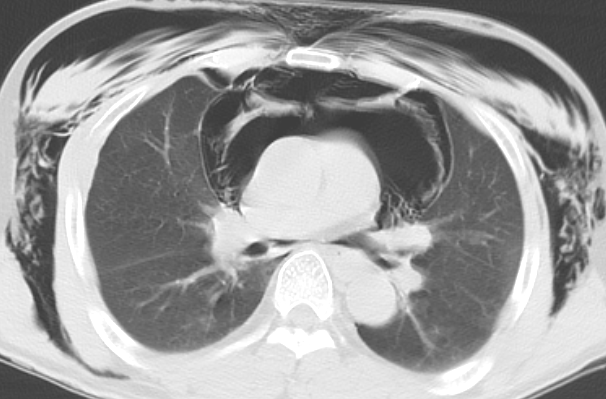

病例41纵膈气肿胸片ct